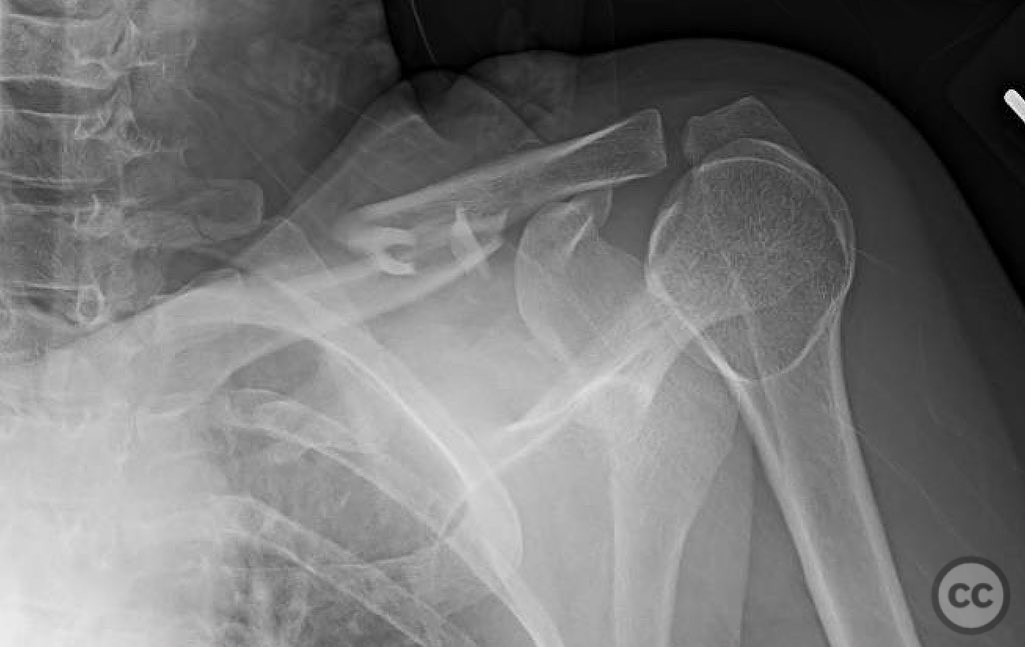

Clinical and radiological findings:  A 35-year-old male presented with an open diaphyseal clavicle fracture following a high-energy motorcycle accident. The fracture was classified as a simple diaphyseal pattern with two butterfly fragments, according to the AO/OTA classification system, specifically 15-B2. The patient exhibited significant soft tissue injury but no neurovascular compromise. Initial radiographs confirmed the fracture pattern, and the wound was thoroughly irrigated and debrided in the emergency department.

Preoperative Plan

Planning remarks:  The preoperative plan involved direct exposure of the fracture site with anatomic clamp reduction. Interfragmentary compression was planned using lag screws for the butterfly fragments, followed by application of a reconstruction plate on the anterior inferior aspect of the clavicle for neutralization.